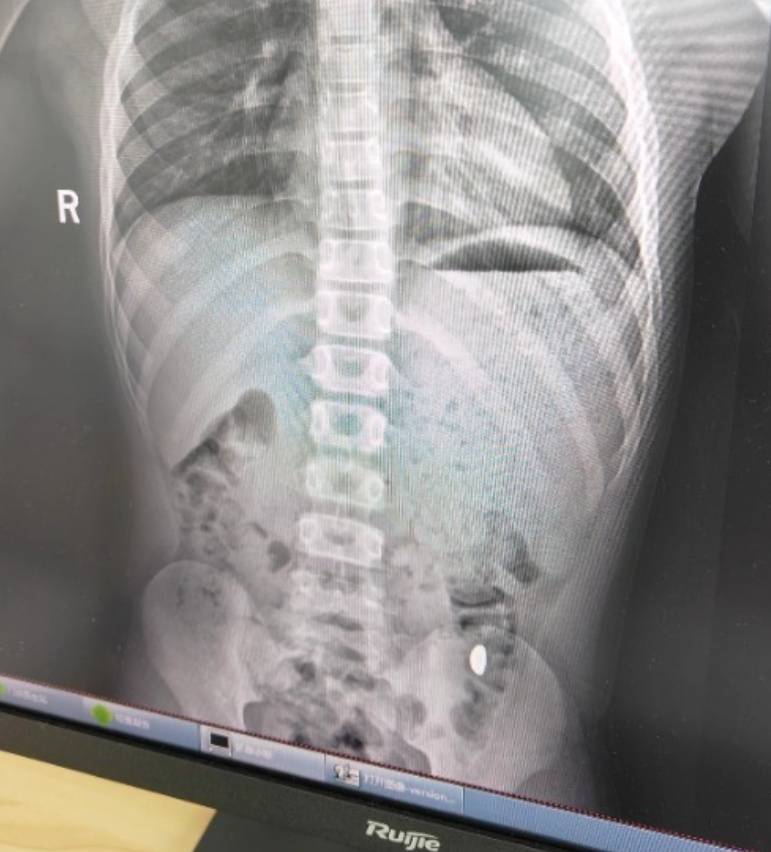

右下加亮点为金豆理财夜市。